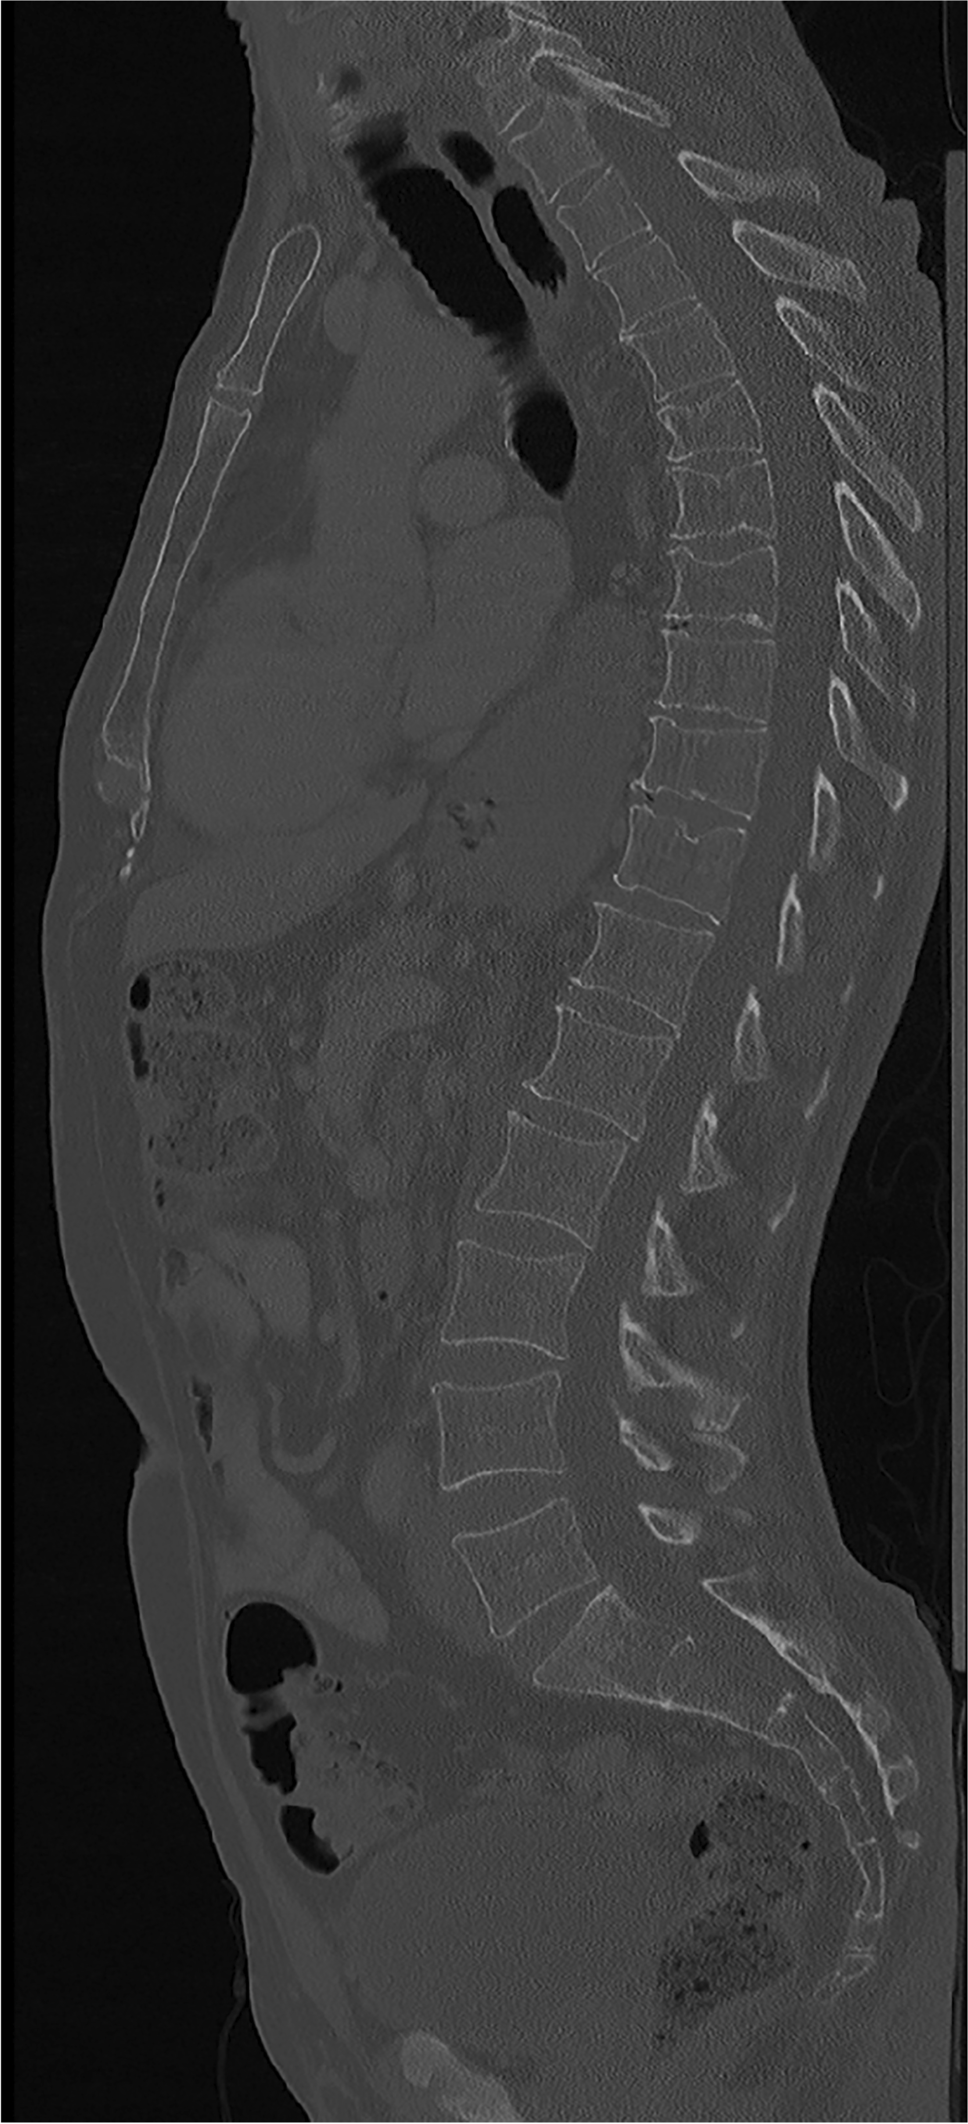

A total of 12.167 thoracolumbar vertebrae were assessed for fractures with most scans covering the entire thoracolumbar spine (Fig. 2). Of the 718 patients, 219 patients showed ≥ 1 osteoporotic VFs (30.5%) and 25 patients showed only pathologic VFs (3.5%). The overall prevalence of osteoporotic VFs was 26.3% in women and 32.5% in men, without significant difference between sexes (p = 0.097). Most fractures occurred at the thoracolumbar junction with the peak at level L1 and at the mid-thoracic spine with a local maximum at level T8 (Fig. 2). An example case of a patient with osteoporotic VFs is shown in Fig. 3.

Fig. 3

Contrast enhanced CT scan of a 61-year-old male patient performed for follow-up of esophageal cancer after esophagectomy showing osteoporotic vertebral fractures at T6–8, T10, and T11. The patient’s medical records and CT imaging report did not include any information related to suspected low bone mass or osteoporosis